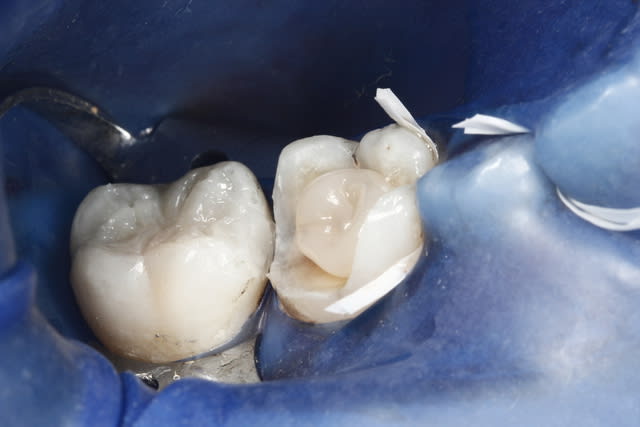

un cas de ce matin.

-avec, IDS (immediate dentin sealing) très pratique pour avoir une étanchéité le jour de la préparation, aurais pu/du se faire sous digue....

- Collage avec composite de stratification chauffé et vibré, très facile pour gérer les excès ...

- Permettra de comparer le vieillissement de l'onlay versus composite direct ...

Oui le compo à été fait le jour du collage, en fait l'amalgame me semblait bien mais aprés dépose de celui sur la 6, j'avais un doute sur une infiltration mésial, j'ai donc déposé le plombage sur 7 le jour de la pose de l'onlay

J'ai monté mon compo en me servant de l'onlay pour modeler la face mésial du composite, puis j'ai collé l'onlay dans un second temps...